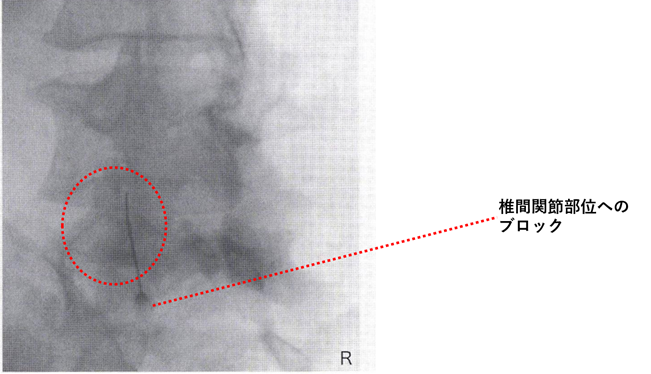

これは標準的な対応ですが、痛みが強くて動けない場合、ペインクリニックでは「神経ブロック注射」を推奨します。痛みの原因となっている神経の近くに局所麻酔薬や抗炎症薬を注入することで、即効性のある除痛が期待でき、痛みの悪循環を断ち切ることができます。また、椎間関節症は,腰神経の後枝内側枝ブロック(または椎間関節ブロック)により診断されます。

下の画像は、透視を使った、腰部の椎間関節へのブロック注射の画像です。

参考 透視画像:臨床スポーツ医学:Vo1,39, No,2〔2022-2)より抜粋一部変更